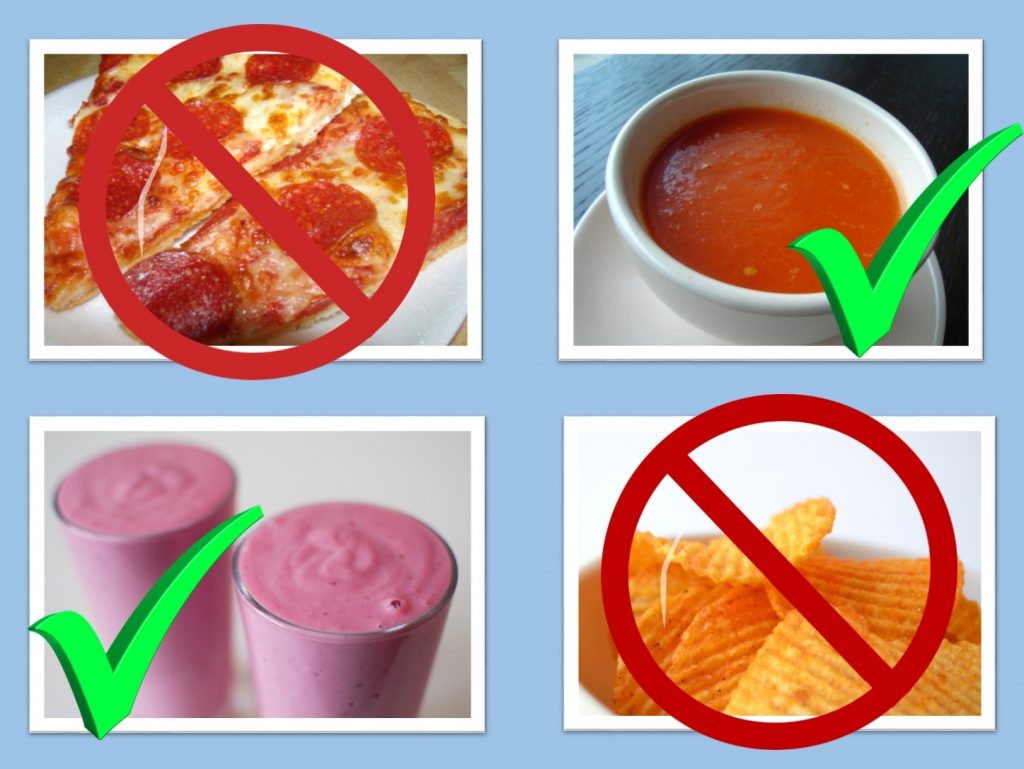

When Can You Eat Solid Foods After Gastric Bypass

When Can You Eat Solid Foods After Gastric Bypass

More picture related to When Can You Eat Solid Foods After Gastric Bypass

Diet After Gastric Bypass Nutrition Planning

Pin On Gastric Bypass Meal Plan Ideas